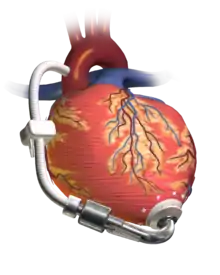

A left ventricular assist device (LVAD) pumping blood from the left ventricle to the aorta, connected to an externally worn control unit and battery pack. | |

A ventricular assist device (VAD) is an electromechanical device that provides support for cardiac circulation, which is used either to partially or to completely replace the function of a failing heart. VADs can be used in patients with acute (sudden onset) or chronic (long standing) heart failure, which can occur due to a variety of reasons (e.g. coronary artery disease, atrial fibrillation, valvular disease, and so forth).[1][2]

Ventricular Assistance

First, VADs can be categorized based on whether they are designed to assist the right ventricle (RVAD) or the left ventricle (LVAD) or to both ventricles (BiVAD). The type of VAD implanted depends on the type of underlying heart disease (e.g. patients with right ventricular failure from pulmonary arterial hypertension may require an RVAD, versus those with left ventricular failure from a myocardial infarction may require an LVAD). The LVAD is the most common device applied to a defective heart (it is sufficient in most cases; the right side of the heart is then often able to make use of the heavily increased blood flow), but when the pulmonary arterial resistance is high, then an (additional) right ventricular assist device (RVAD) might be necessary to resolve the problem of cardiac circulation. If both an LVAD and an RVAD are needed a BiVAD is normally used, rather than a separate LVAD and RVAD.